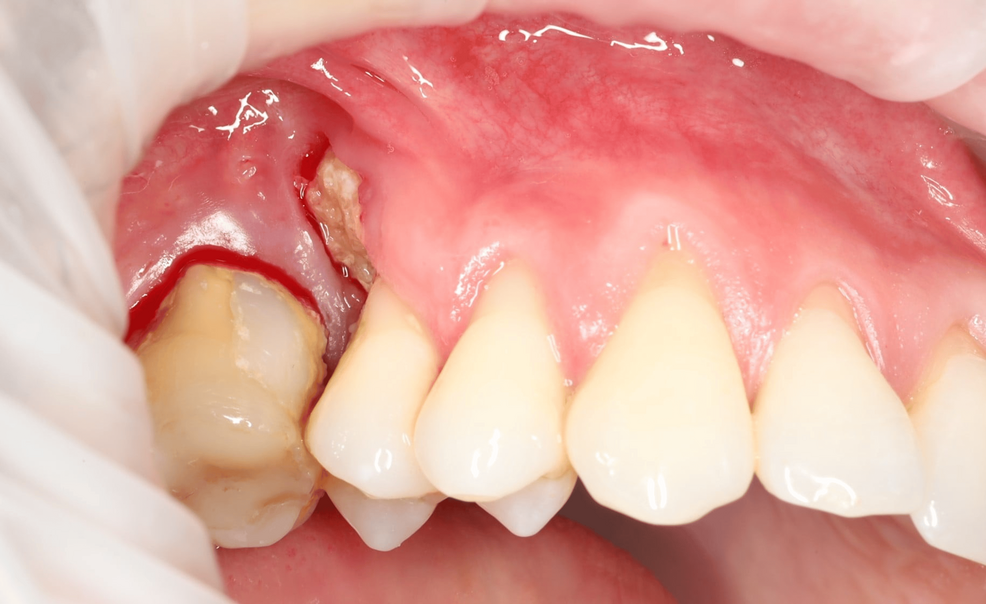

Cementoblastoma

Cementoblastoma - Wikipedia Apical Radiopacities - Radiodontics Cementoblastoma: Features, Diagnosis, and Treatment Cementoblastoma. Classic appearance of a sclerotic tumor fused ... ❇ Benign Cementoblastoma Radiology: ▶ Location: → 78% in ... Cementoblastoma